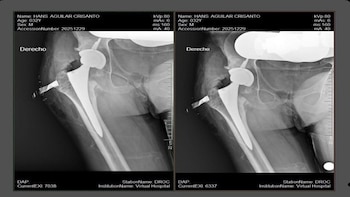

El beneficiario fue Hans Aguilar Crisanto, de 32 años, quien presentaba limitaciones importantes en su movilidad. Gracias a esta intervención, podrá recuperar funciones esenciales y aspirar a una reintegración activa a sus actividades cotidianas.

La elección de una prótesis no cementada de cabeza de cerámica responde a criterios de innovación y eficacia, sobre todo en pacientes jóvenes, ya que facilita una mejor adaptación al hueso y prolonga la vida útil del implante.

Esta alternativa reduce riesgos futuros y favorece una recuperación funcional más completa, evidenciando el compromiso con la actualización continua en técnicas quirúrgicas.